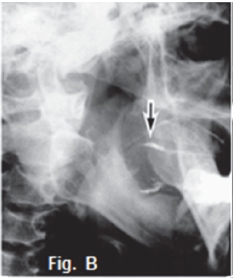

Fig. A is a photograph of a 65 year old male patient presenting with a slow growing swelling of the parotid gland on the right side of the face, which he noticed about eight months ago. Sialography of the parotid gland (Fig. B) shows that contrast medium uptake is prevented by tumour formation, resulting in a poorly imaged right parotid gland (arrow). Fig. C is an axial CT of the same patient demonstrating an ill-defined tumour with an infiltrative margin, indicating malignancy. The right masseter muscle also lacks definition because of infiltration by a malignant tumour (red arrow). A diagnosis of an epidermoid carcinoma was made. The tumour was termed mucoepidermoid by Stewart et al in 1945, who considered it to be divided into benign and malignant types. The WHO regards this tumour as a lesion with malignant potential but believes that, in a variety of clinical instances, it is inappropriate to call any of these tumours "carcinomas". The WHO consider this neoplasm to be intermediate between adenoma and carcinoma. Thirty percent of mucoepidermoid malignancies occur in the salivary glands and appear commonly in the 3rd to 4th decades. The sialogram in Fig. D shows irregular non filling defects suggestive of a malignant pleomorphic adenoma (malignant mixed tumour). The CT sialogram (Fig. E) of the same patient shows an ill-defined tumour mass (arrow). Pathologically, malignant pleomorphic adenoma results from the transformation of the epithelial tissue in a pleomorphic adenoma. These tumours occur predominantly in patients older than 50 years. The transverse T1 weighted MRI scan (Fig. F) of an adenocarcinoma of the right parotid gland shows a poorly defined, non-homogeneouus, infiltrating mass (arrow). Adenocarcinomas most commonly involve the minor salivary glands and submandibular glands, accounting for 5% to 10% of salivary gland tumours. A break in the duct and leakage of contrast medium are sialographic signs of malignancy, and are usually found in epidermoid carcinoma, adenocarcinoma, and high-grade mucoepidermoid carcinoma. However, most of the malignant tumours have a low rate of malignancy.